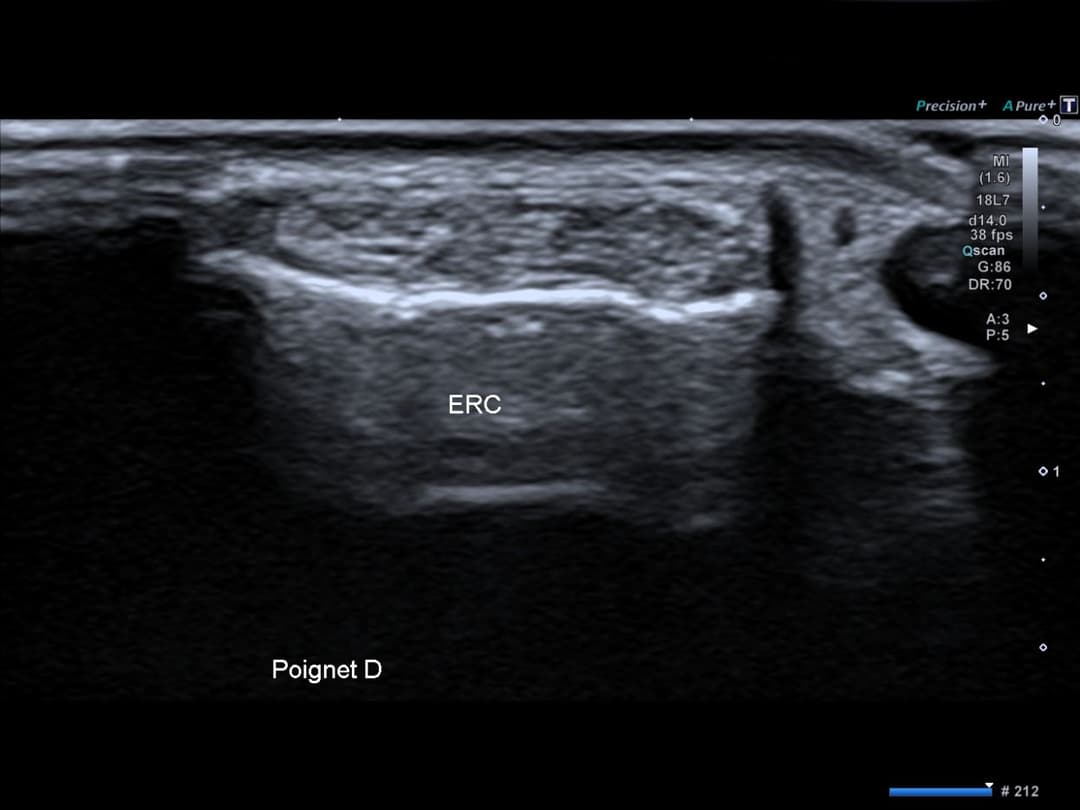

Intégrité des tendons extenseurs radiaux du carpe au niveau du poignet